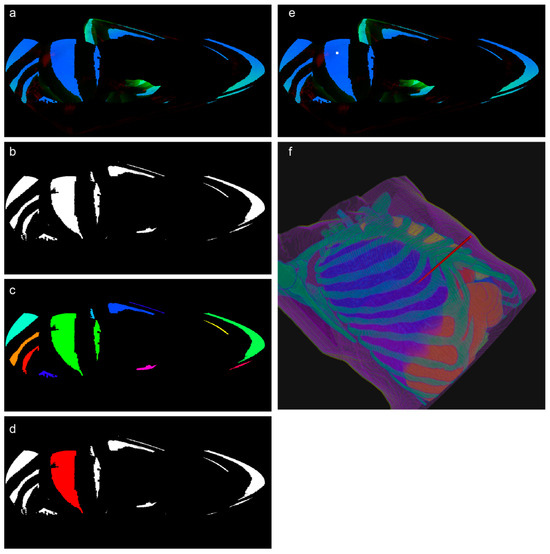

2.4.1. Segmentation Mask Acquisition

2.4.2. Mask Resampling

2.4.3. ROI Cropping

2.4.4. No-Skin Region Removal (Optional Step)

2.4.5. Intensity Calculation

2.4.6. Optimal Path Recommendation

- a.

- Illumination Map Generation and RGB Projection